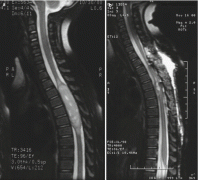

髓内脊髓肿瘤(IMSCTs),如下图所示,是指硬膜内 脊髓肿瘤 的一个亚群,由脊髓内的细胞产生,与相邻结构如神经根或脑膜相对。它们比脑瘤少见得多,据认为占中枢神经系统全部固有肿...

大多数脊髓髓内肿瘤患者起初可以通过尝试切除来治疗。不幸的是,那些不能行总切除或次全切除的患者,只能选择放疗和化疗...